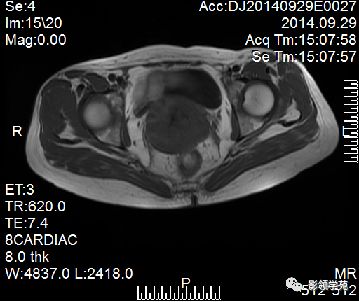

宫颈癌可表现为类圆形或不规则形肿块,在T2WI上表现为均匀或欠均匀的高信号,与正常宫颈基质及宫旁脂肪形成良好的自然对比。

MRI

- Ⅰ期肿瘤:侵犯宫颈基质,T2WI等信号肿块,宫颈管扩大及宫颈纤维基质中断